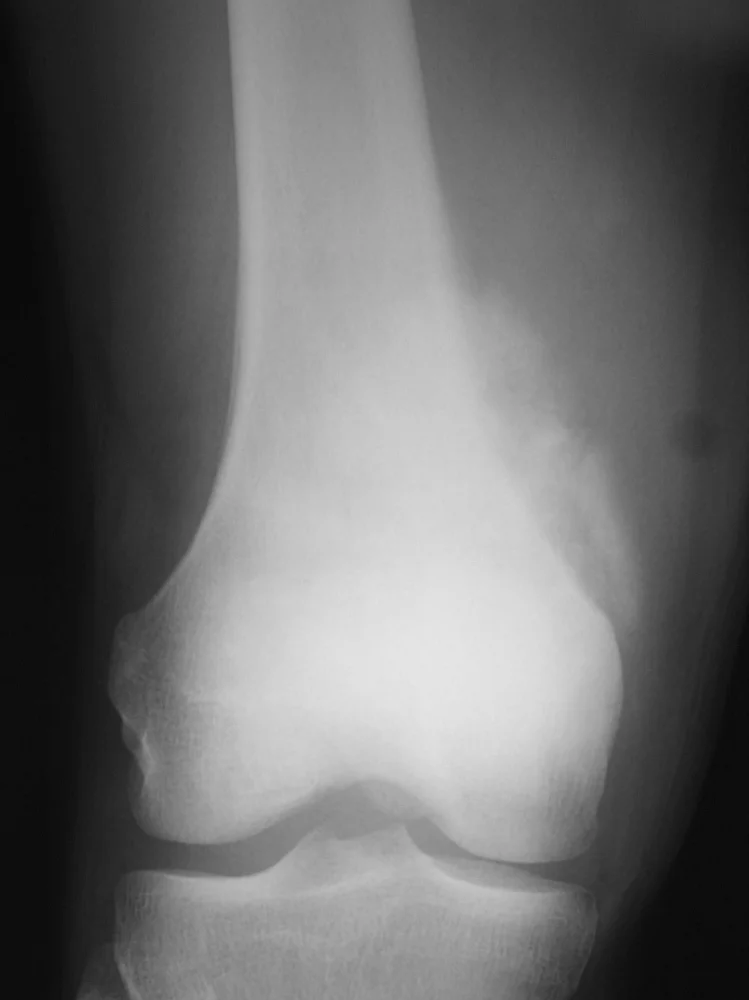

This 18 year old boy had pain in his knee that was not going away over a period of months. Eventually X-rays were done (first image on the left) which show the hallmark findings of osteosarcoma. As seen more closely on the second image, there is a mass adjacent the bone which is calcified. This is almost definitive for osteosarcoma. The last two are MRI images showing the tumor extending up and outside the femur. His tumor was localized to the femur (Stage IIb).